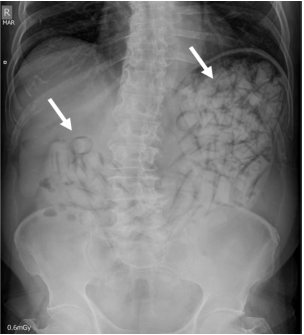

La radiografía de abdomen al ingreso mostró múltiples imágenes radiopacas en el marco cólico sugestivas de cuerpos extraños (Figura 1). Se solicitó una tomografía computarizada (TC) de abdomen con contraste en la cual se describieron hallazgos compatibles con síndrome pilórico secundario a retención gástrica de cuerpos extraños, sin evidencia de tránsito hacia distal (Figura 2). Fue llevado a laparotomía exploratoria identificando marcada distensión de la cámara gástrica; se realizó una gastrotomía y extracción sin complicaciones de 97 cuerpos extraños de látex en forma de dedo con pérdida del recubrimiento de parafina (Figura 3).

Figura 1. Radiografía de abdomen simple. Múltiples imágenes radiopacas en la cámara gástrica sugestivas de cuerpos extraños (flechas blancas).

La radiografía simple es la herramienta más importante para la detección, con una sensibilidad entre 40-90 % dependiendo del tipo y pureza de la droga, material del paquete, tamaño, localización y número de paquetes 1,5,7; la especificidad puede ser tan alta como del 97 % 5. Los signos radiográficos que pueden identificarse incluyen: múltiples cuerpos extraños radiopacos y signos de “doble condón”, “tic tac”, paralelismo, envoltura hiperdensa o multiplicidad de cuerpos extraños con aire atrapado entre ellos 1,4,5.